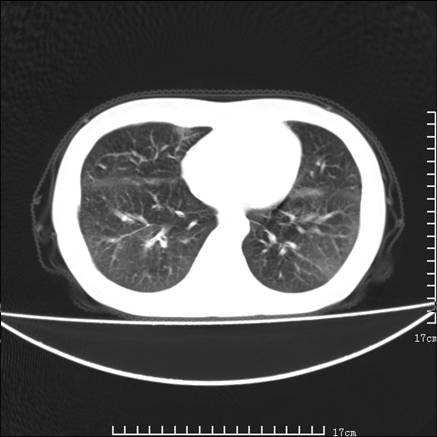

女,46岁,患胃溃疡多年,溃疡大小约1.0cm左右,后于5年前手术,病理为胃癌。主诉:半月前感冒后胸闷,气短,有咳嗽,无明显咳痰,无发热。偶有腰背部不适。

以下为高分辨扫描图像

胸椎9、12椎体可见斑片状破坏,余椎体及肋骨均未见明显异常改变,故不再上传。请原谅。

双肺小叶间增厚,双肺散布粟米影和磨玻璃状影,以双肺上叶为重。结合病史考虑转移(癌性淋巴细管炎)可能性大。

合并征象为:纵隔淋巴结增大,胸腔积液,肺多发随机分布的小结节等。

1、结节病,多位于肺的上中部和后部,呈向心性分布,造成近肺门区的支气管血管束周围间质和胸膜下间质增厚,小叶间隔增厚不明显,即使增厚也较为局限

2、尘肺,可以通过病史,肺外周为主的多发结节,胸膜假斑,聚合成的团块,间质纤维化等鉴别

3、肺水肿,肺水肿可以造成肺间质的增厚,为光滑的增厚且常为双侧对称性分布。